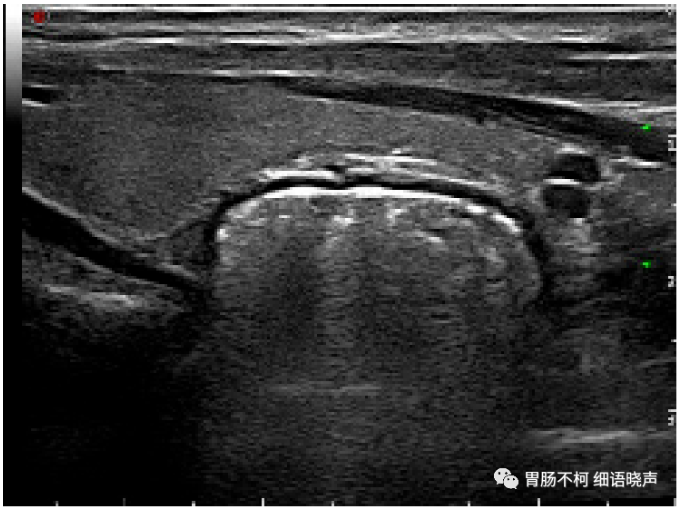

病例二:甲状腺左叶后方强回声型咽食管Killian-Jamieson憩室(此病例由杭州市第一人民医院韩志江主任提供)。

食道左侧壁见一囊袋状突起,边缘光滑。